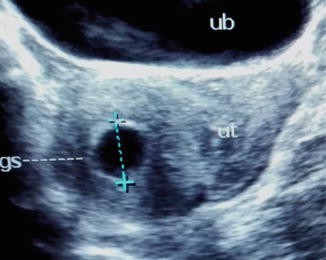

Our affordable early viability private pregnancy scan / 6 week / dating scan is designed to provide you with reassurance in the early stages of your first trimester . We will assess the viability of the pregnancy i .e . visualise fetal heartbeat, assess ectopic pregnancy, vaginal bleeding or pelvic pains & determine if single or multiple pregnancy .

We are Open, Covid-19 Regulations applied . An Early Pregnancy Scan , also called a Viability or Dating Ultrasound scan , will confirm a pregnancy, confirm the gestation age and establish an Estimated Due Date (EDD) . An Early Pregnancy Ultrasound Scan can be performed from 6 weeks of pregnancy at our Harley Street, London clinic or our Alderley Edge, Cheshire clinic .

Early, dating and viability scans (6 - 15 weeks) Why have an early pregnancy scan ? . . . How is the scan carried out? Under 10 weeks the best way to see your baby and get clearer images is by carrying out a transvaginal scan (internal scan ) . However, if you would prefer to come with a full bladder we can start by scanning you this way and the . . .